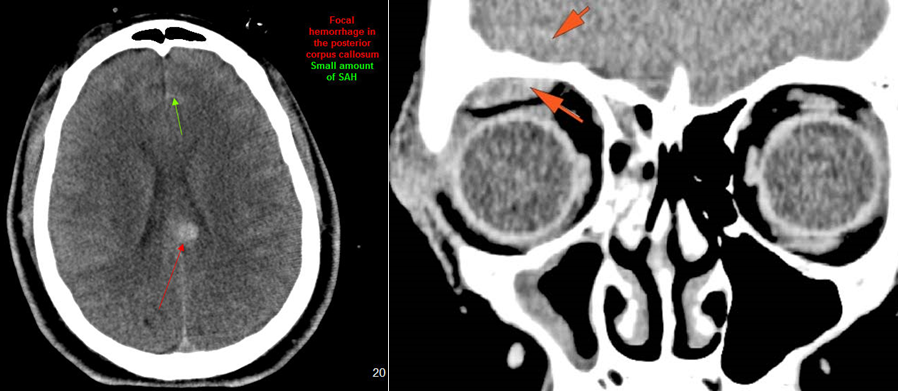

There is subarachnoid bleeding. [Yes/No]

There is evidence of parenchymal brain injury. [Yes/No]

There is evident subretinal, subchoroidal or intravitreous hemorrhage. [Yes/No]